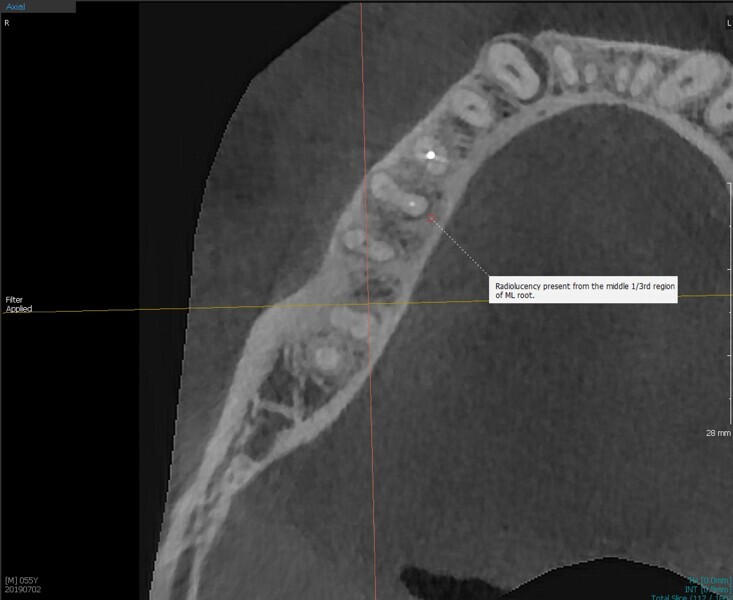

Fig.2a: Pre-op CBCT images of tooth #46: No obturation material in the distal and mesiobuccal canal (a); scanty obturation of the canals and breach of the floor of the pulp chamber, no obturation beyond a few millimetres down the orifice (b & c); radiolucency in the furcation area and periapical region of both roots (d -g).

Fig.2b: Pre-op CBCT images of tooth #46: No obturation material in the distal and mesiobuccal canal (a); scanty obturation of the canals and breach of the floor of the pulp chamber, no obturation beyond a few millimetres down the orifice (b & c); radiolucency in the furcation area and periapical region of both roots (d -g).

Fig.2c: Pre-op CBCT images of tooth #46: No obturation material in the distal and mesiobuccal canal (a); scanty obturation of the canals and breach of the floor of the pulp chamber, no obturation beyond a few millimetres down the orifice (b & c); radiolucency in the furcation area and periapical region of both roots (d -g).

Fig.2d: Pre-op CBCT images of tooth #46: No obturation material in the distal and mesiobuccal canal (a); scanty obturation of the canals and breach of the floor of the pulp chamber, no obturation beyond a few millimetres down the orifice (b & c); radiolucency in the furcation area and periapical region of both roots (d -g).

Fig.2e: Pre-op CBCT images of tooth #46: No obturation material in the distal and mesiobuccal canal (a); scanty obturation of the canals and breach of the floor of the pulp chamber, no obturation beyond a few millimetres down the orifice (b & c); radiolucency in the furcation area and periapical region of both roots (d -g).

Fig.2f: Pre-op CBCT images of tooth #46: No obturation material in the distal and mesiobuccal canal (a); scanty obturation of the canals and breach of the floor of the pulp chamber, no obturation beyond a few millimetres down the orifice (b & c); radiolucency in the furcation area and periapical region of both roots (d -g).

Fig.2g: Pre-op CBCT images of tooth #46: No obturation material in the distal and mesiobuccal canal (a); scanty obturation of the canals and breach of the floor of the pulp chamber, no obturation beyond a few millimetres down the orifice (b & c); radiolucency in the furcation area and periapical region of both roots (d -g).